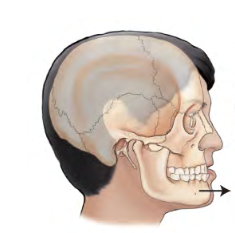

Protraction

movement forward from a normal position